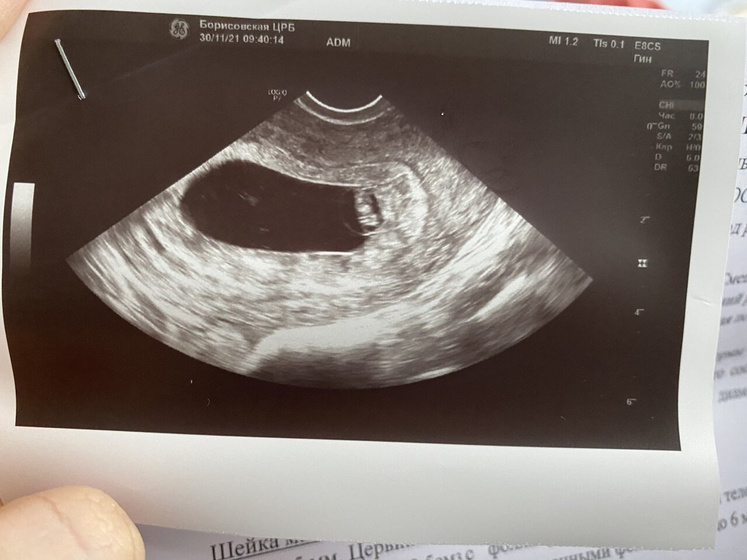

В полоски матки: Хорион перекрывает область внутреннего зева.

Заключение: 7 недель низкого расположения хориона